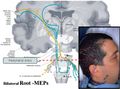

- Bilateral Electric Transcranial Stimulation.jpg 800 × 434; 57 KB

- Bilateral Root-MEPs.jpg 800 × 592; 71 KB